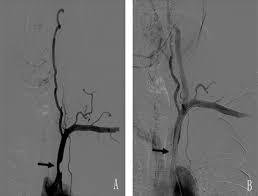

Pseudoaneurysm/

Arteriovenous fistula

- recent arterial access

- antiplatelet

- anticoagulant

- access site swelling

- access site pain

- access site ecchymosis

- pulsatile mass

- systolic bruit

- palpable thrill

- continuous bruit (holosystolic/diastolic)